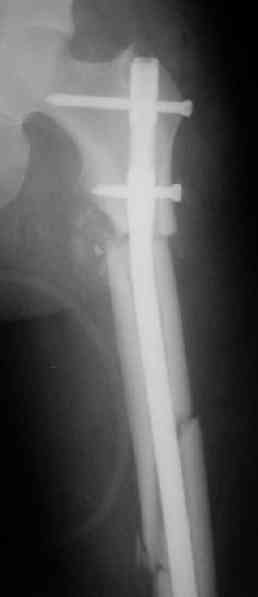

Вот несколько. С тисками и трубой на днях сделаем.

"Судя по уровню перелома, винты в шейку избыточны, подойдет и диафизарный гвоздь. Все, что нужно, это тиски и труба. Загнуть сразу ниже отверстий градусов на 8-10, и вся недолга. Последние годы у нас это рутинная практика. Предызогнутые еще с завода гвозди неудобны тем, что они уже правый-левый."

Конечно. Чтобы не сломать, лучше проложить в тиски сразу ниже отверстий полоску металла, чтобы там создалась концентрация напряжений при изгибе, а не на уровне отверстия.

Гвозди с латерализованным проксимальным концом сейчас становится мэйнстримом, поскольку трохантерная точка входа во всех отношениях

благоприятнее f. piriformis.

Моделирование титановых заготовок, в том числе трубой в тисках, при остеосинтезе по Звереву-Ключевскому - тоже широко распространенная

практика, и бедренные гвозди там тоже достаточно мощные...